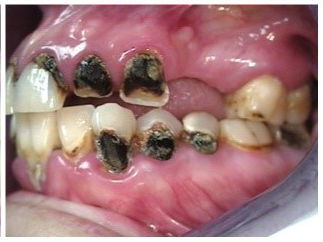

Often, the most visually striking manifestation of long-term meth use—known as “meth mouth”—is caused by the lack of saliva combined with an increase in soda drinking and extremely poor oral hygiene. This typically leads to meth abusers experiencing a large amount of caries. Decay begins with occlusal and facial caries and progresses rapidly, decaying to the bone level and often leaving only roots (Figure 1 through Figure 3).16

Fig 3. After 5 years of meth use in a 22-year-old male patient, cervical decay and coronal fractures were evident.

Figure 3

Fig 4 through Fig 6. Patient’s oral condition after 6 years of meth use.